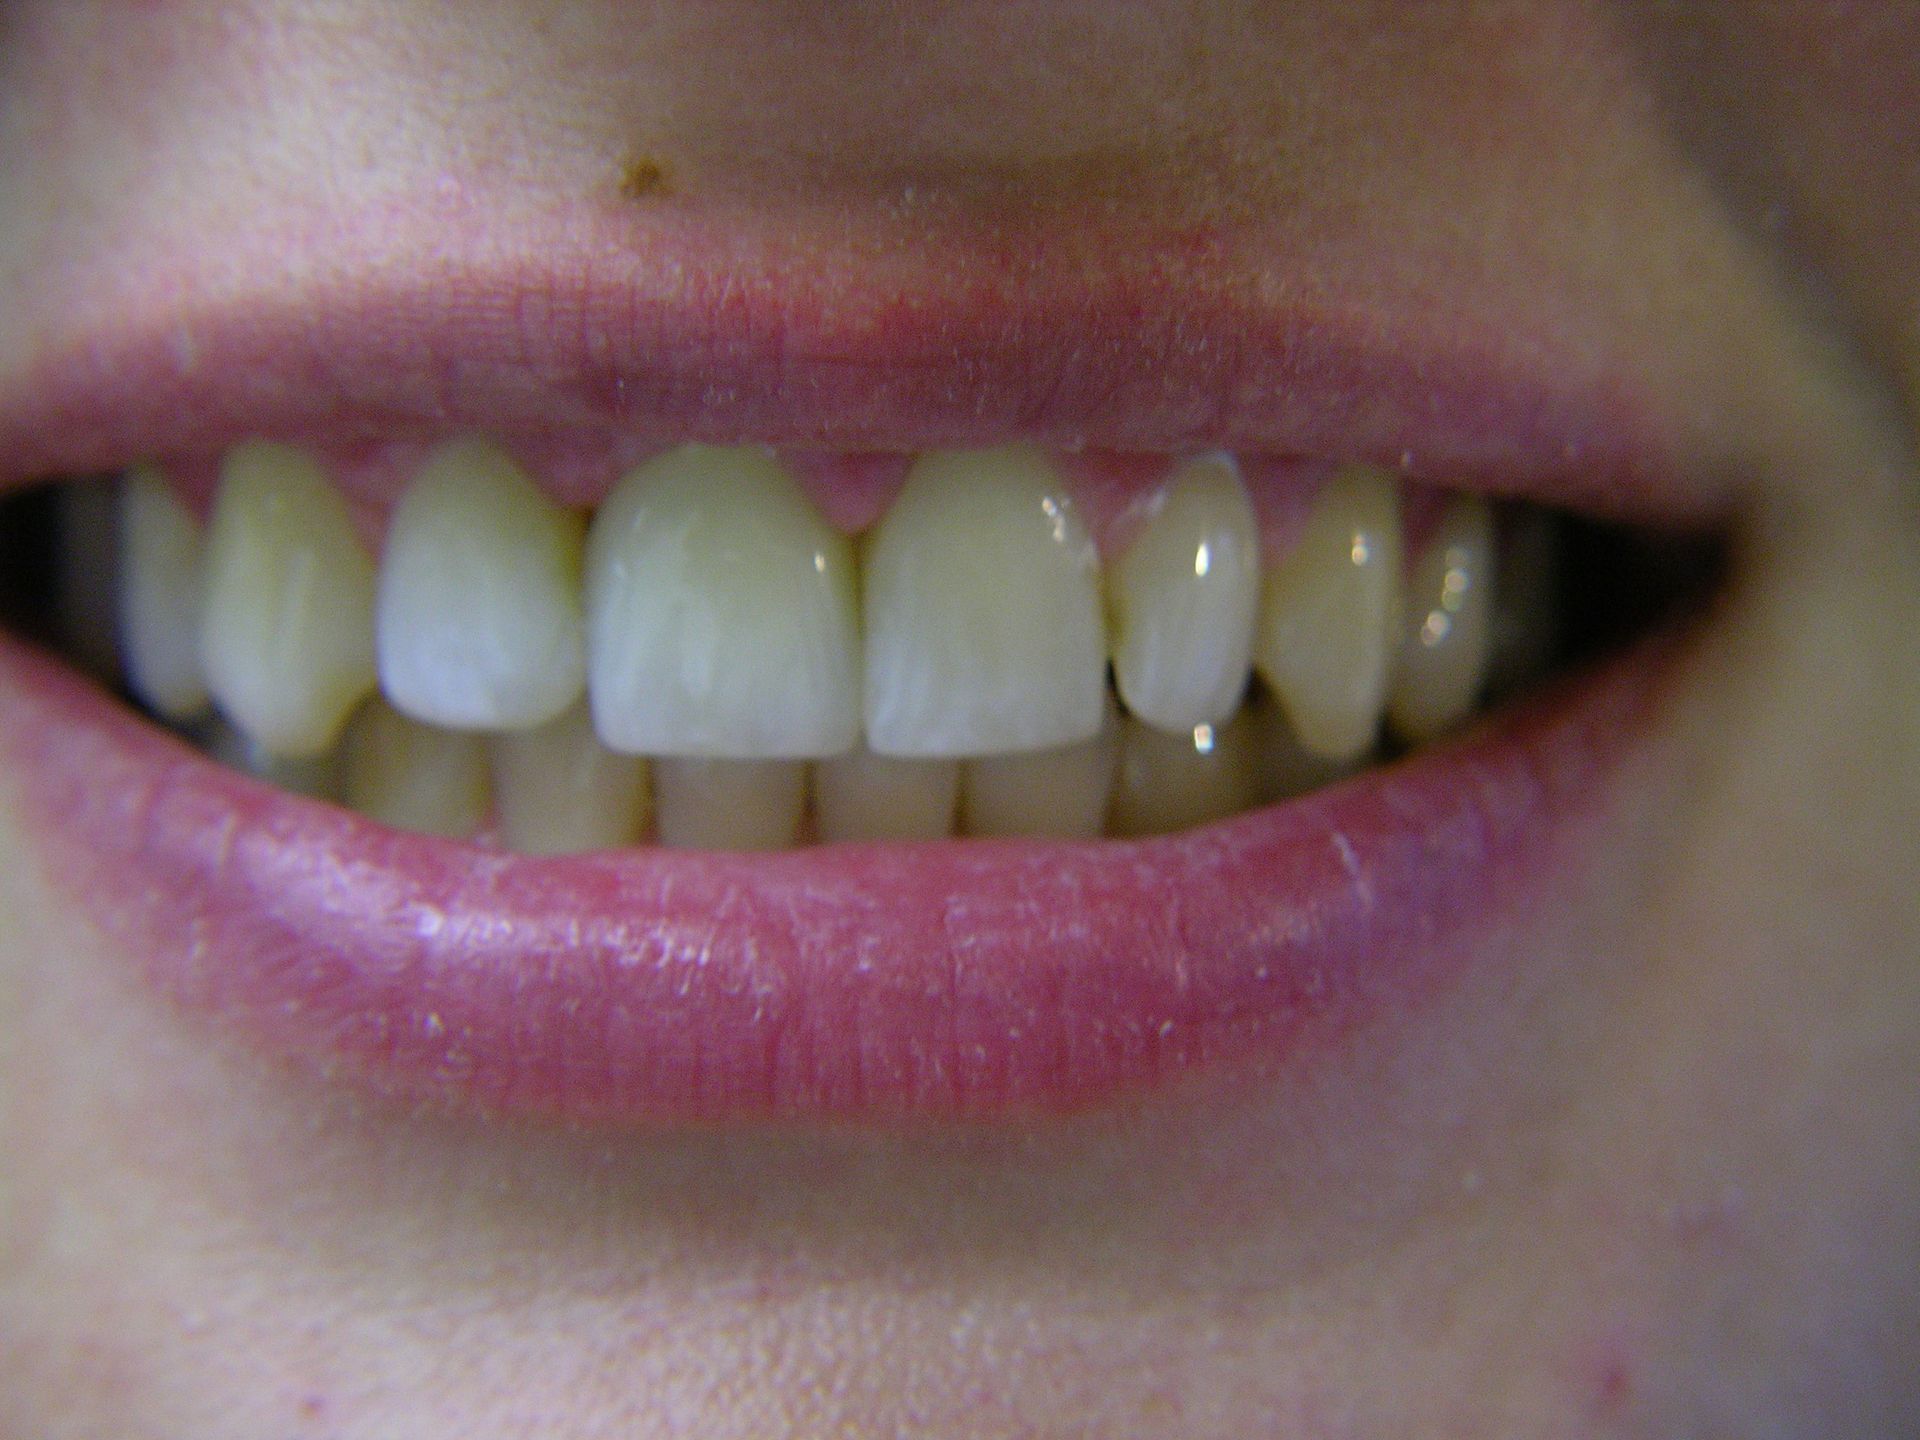

Beispiele von Versorgungen